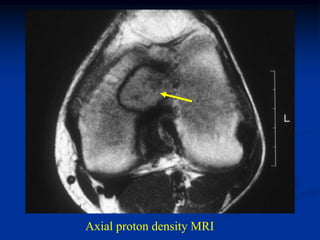

Case #121

17 year female

periosteal chondroma

distal femur

Bone scan

CT scan

Axial proton density MRI

Sagittal proton density MRI

Sagittal T-2 MRI

Photomic